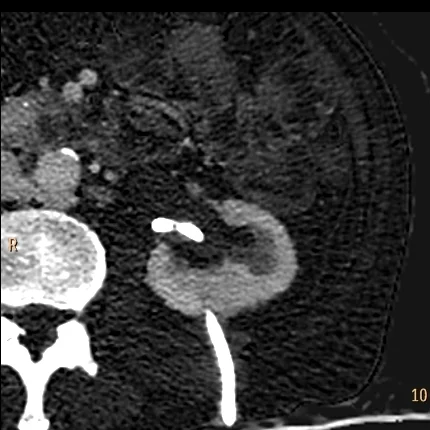

64 year old male with history of bladder cancer, presents with left flank pain. Nephrostomy tube in place, with bloody output. Routine CT of the abdomen performed with contrast shows a "filling-defect" in the left renal pelvis, attenuation about 68 HU. Is it tumor?

Conventional CT: Is that a mass in the left renal pelvis? Note the nephrostomy tube.